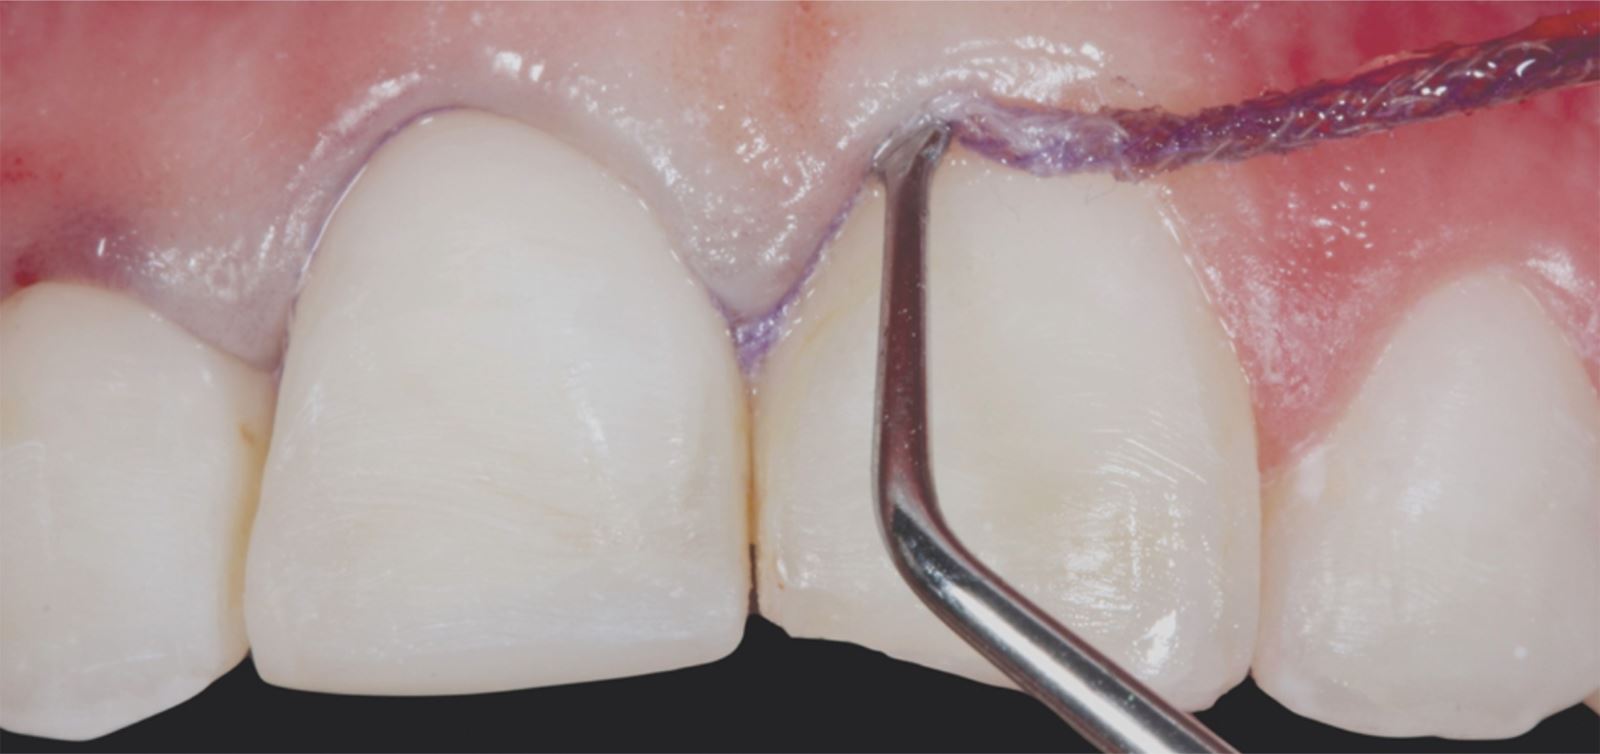

Příprava sulku:

Do gingiválního sulku byla vložena pletená retrakční vlákna Ultrapak™ velikosti #0 k přípravě pro leptání.

Leptání nepreparované skloviny:

Nepreparovaná sklovina byla leptána 35% kyselinou fosforečnou Ultra-Etch po dobu 30 sekund.

Aplikace a ztenčení adheziva:

Adhezivum Peak Universal Bond bylo aplikováno a ztenčeno vzduchem se současným odsáváním.

Cementace:

Fazety byly cementovány pomocí pryskyřičného cementu PermaShade™ LC v odstínu Translucent (není dostupný v Evropě).